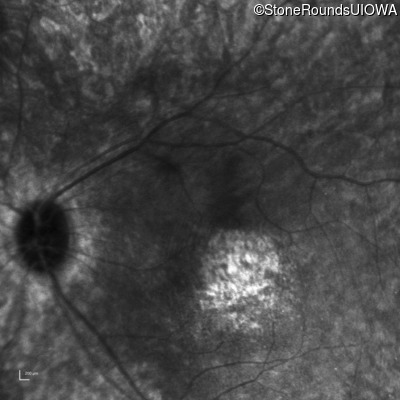

Infrared Fundus Photograph - Left - Hand Motion 6" sc

Exemplar